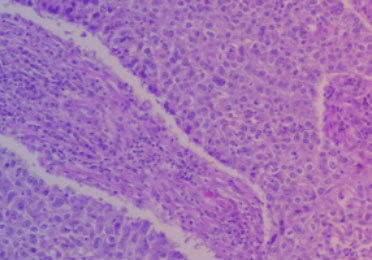

Neben der Symptomatik, einer körperlichen Untersuchung und dem Blutbild ist für die sichere Diagnose eine Gewebsbiopsie notwendig. Dafür wird meist ein Lymphknoten entnommen.